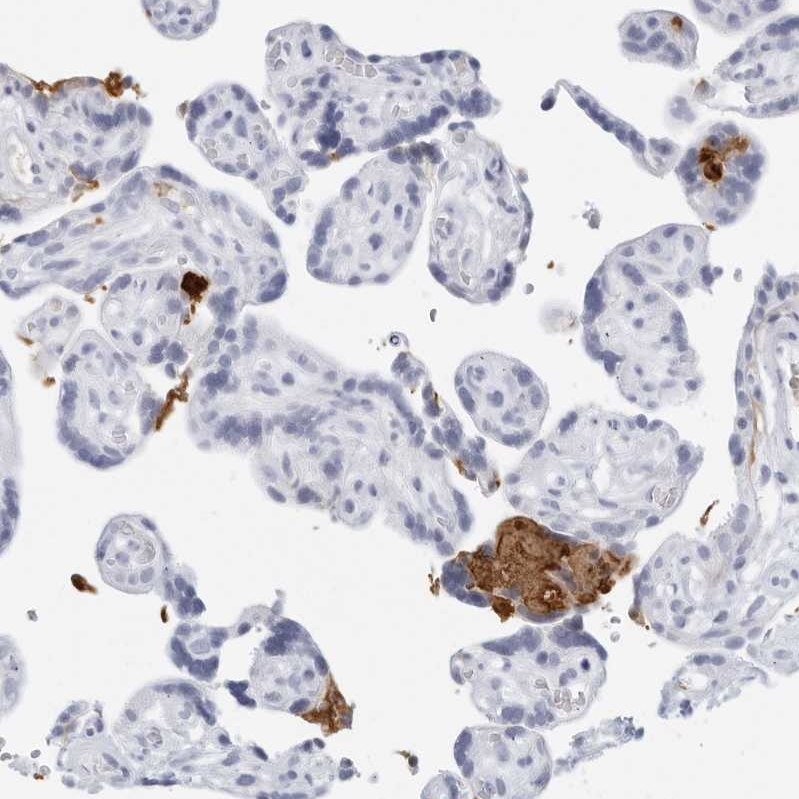

Immunohistochemical staining of human placenta shows strong positivity in plasma.